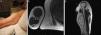

We present a 73-year-old right-handed Jehovah's Witness with a history of mild polio affecting the right arm. MRI showed a slow-growing, cystic mass in the right biceps, originating from the MCN and suggestive of schwannoma. Surgery achieved gross total resection without nerve damage. Histopathology confirmed a cystic schwannoma.